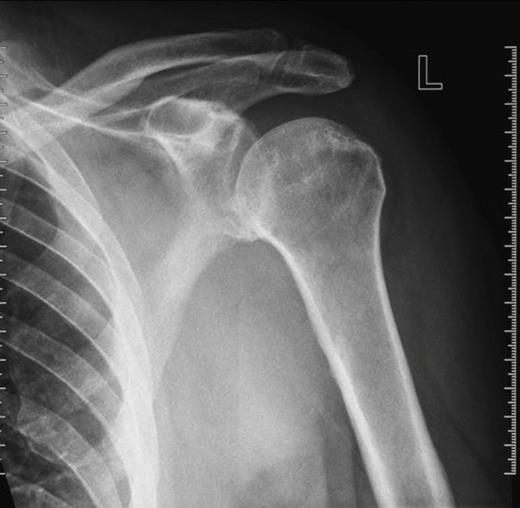

An 80 year old man sustained an injury to his left shoulder during a fall. As a result of the intoxication the history of the mechanism of injury was poor. The gentleman was not taking aspirin or other anticoagulants. On examination movements of the shoulder girdle were reduced secondary to pain. Neurological examination of the left upper limb was normal, as was vascular state of the left arm. X-rays of the joint showed no bony injury (figure 1). Ultrasound showed a large periarticular haemarthrosis and an associated tear in the rotator cuff. Conservative therapy was adopted and the patient was discharged to the rehabilitation ward after two weeks.